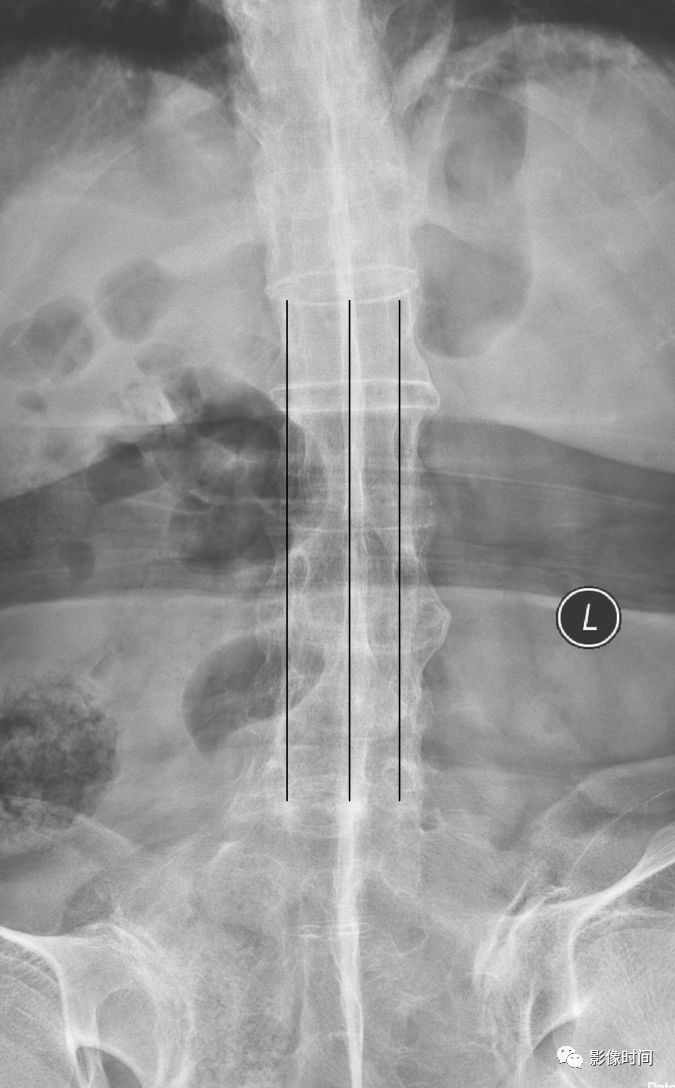

电车轨道征

电车轨道征(trolley-track sign)

电车轨道征是指在正位 X 线片上,强直性脊柱炎患者由于棘上及棘间韧带骨化,两侧小关节囊骨化强直,形成竖向排列的三条高密度线,类似无轨电车的轨道,故而得名。

典型病例

63 岁女性,强直性脊柱炎。正位 X 线片示由于棘上及棘间韧带骨化以及关节突关节强直,呈现电车轨道征。